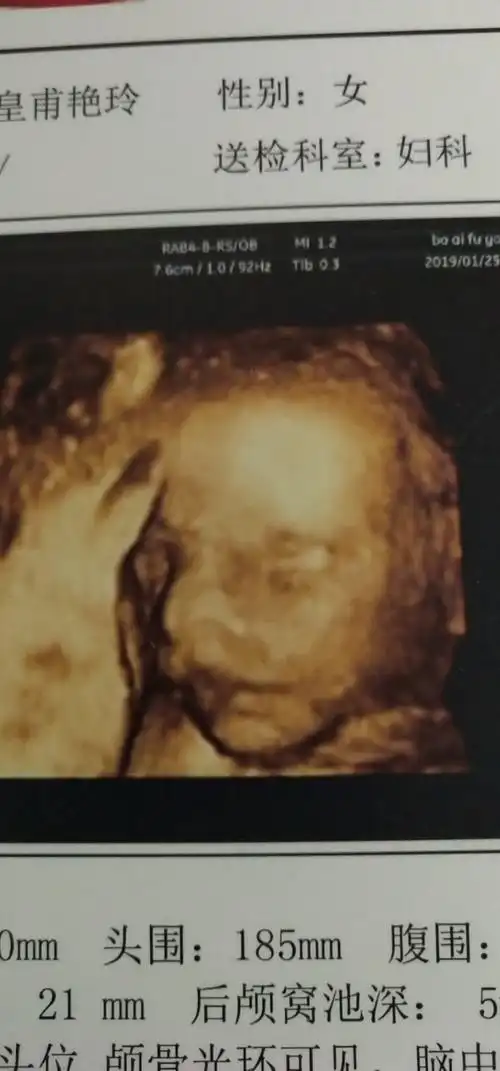

愉快!四维彩超图片"龟龙麟凤"-第2张图片-凯飞博客